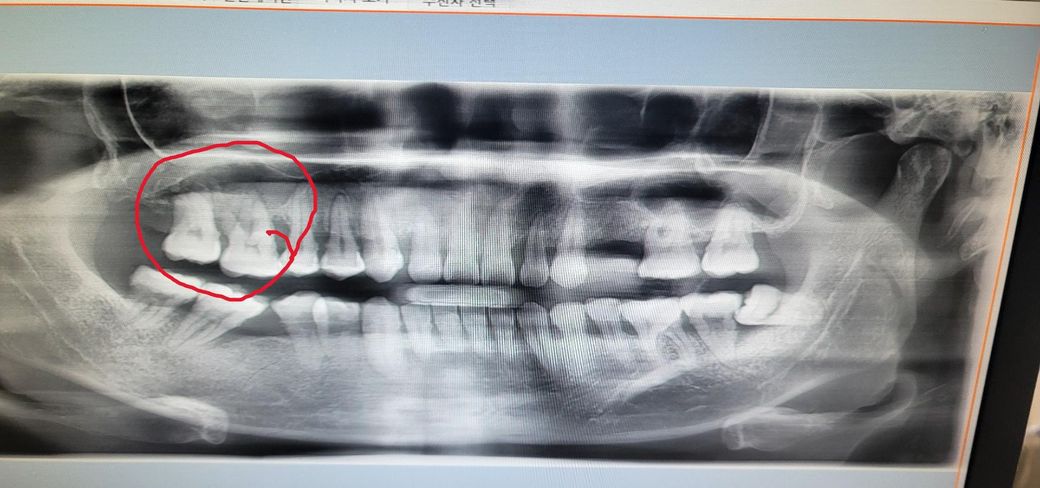

오른쪽 어금니를 보시고는 치아 뿌리에 염증이 있어서 치아 뿌리가 녹아서 부비동염이 온 것 같다며 치과를 가셔서

이후 동네 치과를 가서 진료를 보고 엑스레이를 찍어보니 사진에 오른쪽 끝에 어금니 두개가 살짝 흔들리면서

치아 속에 염증이 차있는 거 같다. 발치를 해야 할 거 같다고 하셨습니다.

• 2번 째 사진

치아떄문에 생긴 상악동 염증이라면 발치를 하시고 나서 상악동의 염증도 같이 제거를 하시는게 좋을것같습니다. 이미 잇몸뼈가 많이 소실된 상태 같습니다.

사진으로 봤을 경우 치아 주변의 치조골이 이미 손실된것으로 보입니다.

치아를 지지하고 있는 치조골이 손상되면 치아를 살리지 못하는 경우가 많기 때문에 발치를 하게 됩니다.

2. 상악동 염증이 꽤 크네요. 이게 치성원인이라면 발치는 불가피하고 발치 후 상악동 세척술 필요합니다.